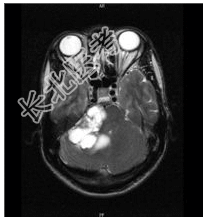

- [材料题] 患者男,37岁,右耳听力丧失数月。查体:右耳听力丧失,视力正常,余神经体征阴性。行头颅MR平扫及增强检查。

- 简答题1、患者的诊断及依据是什么?

- 简答题2、鉴别诊断有哪些?